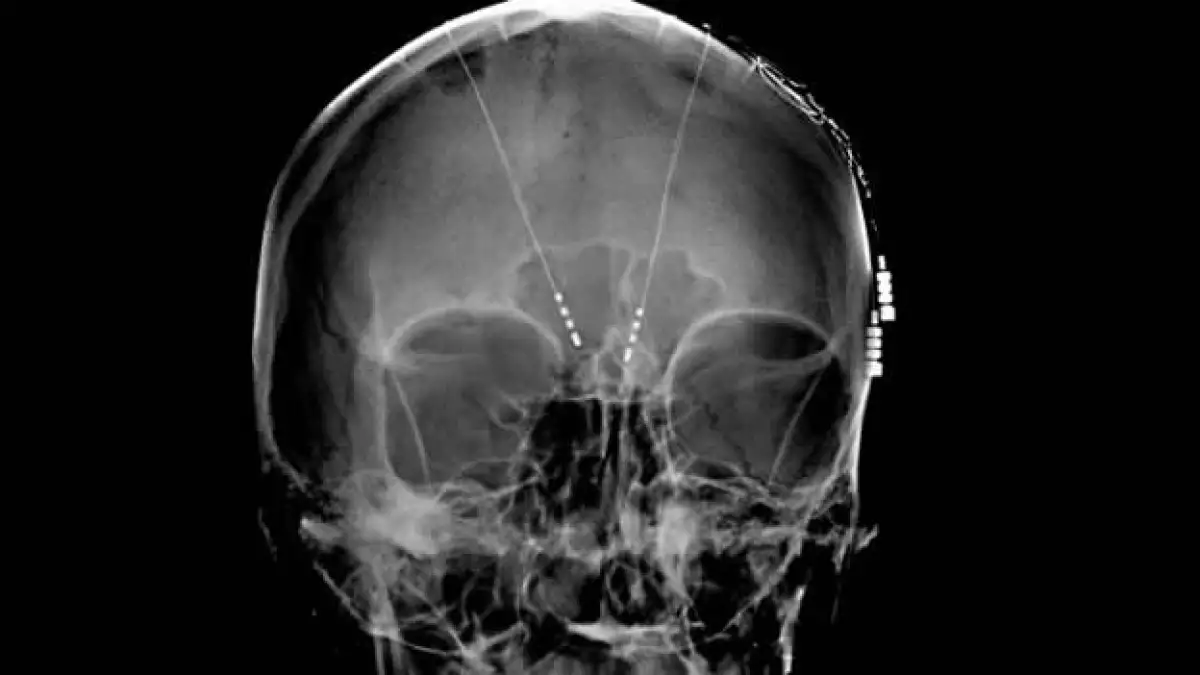

El procedimiento, llamado estimulación cerebral profunda (DBS, por sus siglas en inglés), utiliza un dispositivo similar a un marcapasos para producir una pequeña y constante descarga eléctrica en circuitos específicos del cerebro que controlan nuestro estado de ánimo.

El blanco de la cirugía de DBS es la materia blanca que se encuentra justo debajo de una estructura cerebral del tamaño de un chícharo conocida como Área 25. Experimentos previos de Mayberg habían identificado al Área 25 como una caja de conexiones de los circuitos cerebrales vinculados a nuestro estado de ánimo. Ella lo llama “un cabecilla”. Utilizando poderosa tecnología de imagenología, Mayberg encontró que el Área 25 parece ser hiperactiva en los pacientes deprimidos.